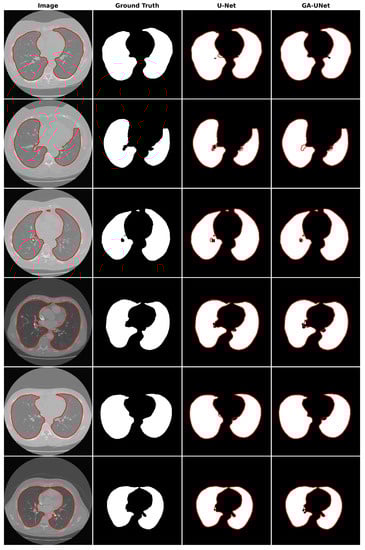

For the qualitative analysis, we show some precise and promising segmentation results in Figure 8 to visually compare our method with the original U-Net [12] model. The lung segmentation result depicted in Figure 8 is deemed satisfactory, as the proposed approach GA-UNet was able to almost completely segment the lung from the CT scan images. But in some instances, as shown in rows 2 and 4, it missed a small portion of the lung.

Figure 8.

Segmentation results on lung segmentation dataset. From left to right, the columns represent in order: the input image, ground truth, U-Net prediction, and GA-UNet prediction. The red curves represents the actual area of the lung.